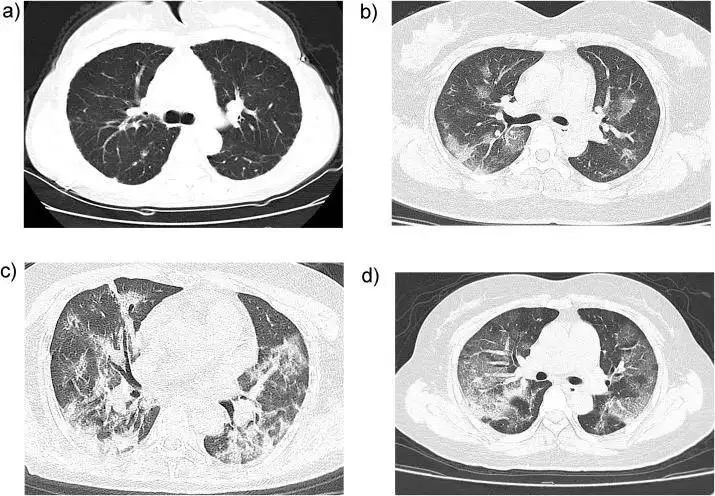

移動車載CT車診斷案例:新冠肺炎CT影像照片是什么樣的?

新冠肺炎患者的CT表現(xiàn),早期多呈現(xiàn)多發(fā)的小斑片影及間質(zhì)的病變

以肺外帶明顯,會逐漸發(fā)展為雙肺多發(fā)的磨玻璃影、浸潤影。

嚴(yán)重的患者會出現(xiàn)肺的實(shí)變影像,以及胸腔積液。

除肺部CT的影像變化,還需要結(jié)合流行病學(xué)接觸史、臨床表現(xiàn)及病原學(xué)證據(jù),才能確診為新型冠狀病毒肺炎。